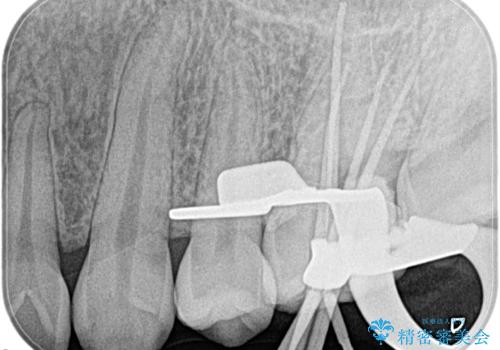

- 奥歯がズキズキ痛いことを主訴に来院されました。

検査の結果、診断を症候性不可逆性歯髄炎、症候性根尖性歯周炎とし抜髄を行っております。

主訴である痛みを解決することができました。無菌的治療を行うことで、根尖性歯周炎の予防にも期待できる治療を行いました。